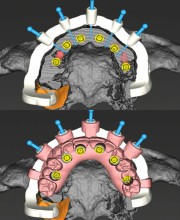

در مرکز تخصصی دکتر محمودی، از بهترین مواد و تکنولوژیهای روز دنیا برای انجام ایمپلنت دندان استفاده میکنیم. شما میتوانید مطمئن باشید که نتیجه کار دائمی و با کیفیت خواهد بود.

ایمپلنت دندان فرآیندی ساده است که با تکنولوژیهای پیشرفته ما، بدون درد و با حداقل زمان به نتیجه میرسد.

مرکز تخصصی دکتر محمودی با بیش از سالها تجربه در ارائه خدمات دندانپزشکی پیشرفته، به شما این اطمینان را میدهد که درمان شما با بهترین کیفیت و در محیطی کاملاً استریل و بهداشتی انجام خواهد شد. پزشکان ما از تکنیکهای نوین و تجهیزات روز دنیا برای انجام ایمپلنت استفاده میکنند.